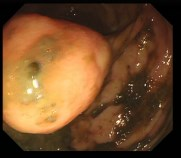

Vision foundation models like the Segment Anything Model (SAM), pretrained on large-scale natural image datasets, often struggle in medical image segmentation due to a lack of domain-specific adaptation. In clinical practice, fine-tuning such models efficiently for medical downstream tasks with minimal resource demands, while maintaining strong performance, is challenging. To address these issues, we propose BALR-SAM, a boundary-aware low-rank adaptation framework that enhances SAM for medical imaging. It combines three tailored components: (1) a Complementary Detail Enhancement Network (CDEN) using depthwise separable convolutions and multi-scale fusion to capture boundary-sensitive features essential for accurate segmentation; (2) low-rank adapters integrated into SAM's Vision Transformer blocks to optimize feature representation and attention for medical contexts, while simultaneously significantly reducing the parameter space; and (3) a low-rank tensor attention mechanism in the mask decoder, cutting memory usage by 75% and boosting inference speed. Experiments on standard medical segmentation datasets show that BALR-SAM, without requiring prompts, outperforms several state-of-the-art (SOTA) methods, including fully fine-tuned MedSAM, while updating just 1.8% (11.7M) of its parameters.